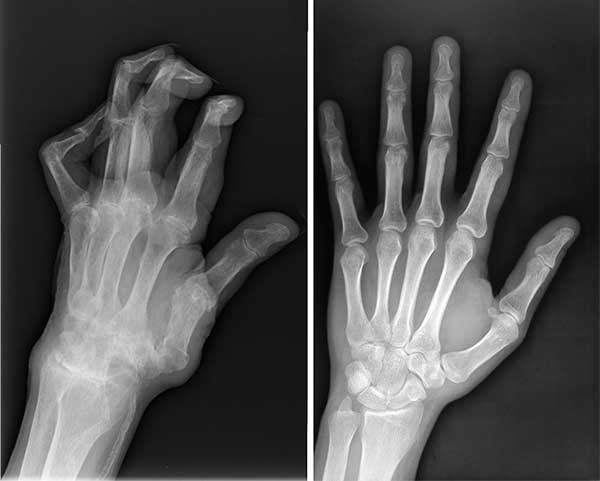

ภาพเอกซเรย์เปรียบเทียบก่อนและหลังทาน Movinix ของสามี

ภาพเปรียบเทียบสภาพมือของสามีก่อนและหลังทาน Movinix